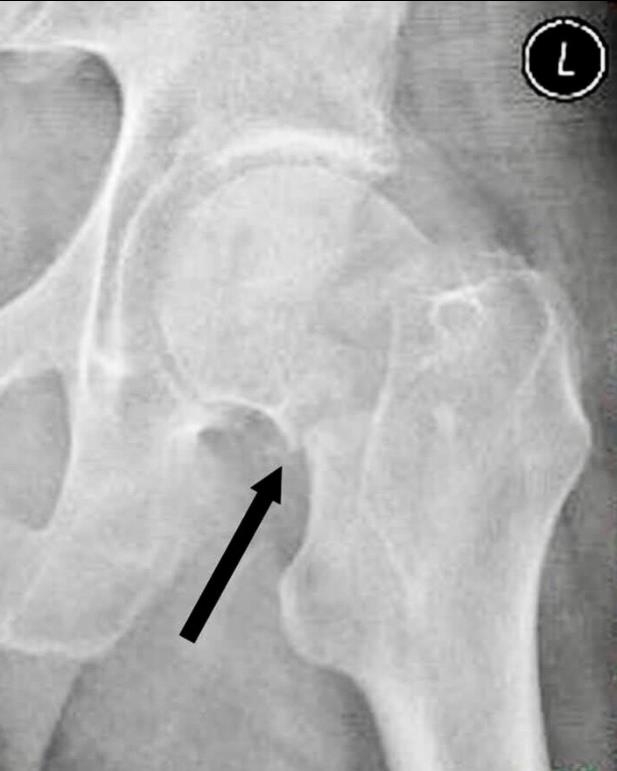

2、阴性支撑是指近侧骨折断端(股骨颈、头)的内下缘突向股骨颈远骨折端内上缘的内侧。阴性支撑容易导致复位的股骨头移位,继而发生内翻,内固定失败率高。

图4 阴性支撑不稳定